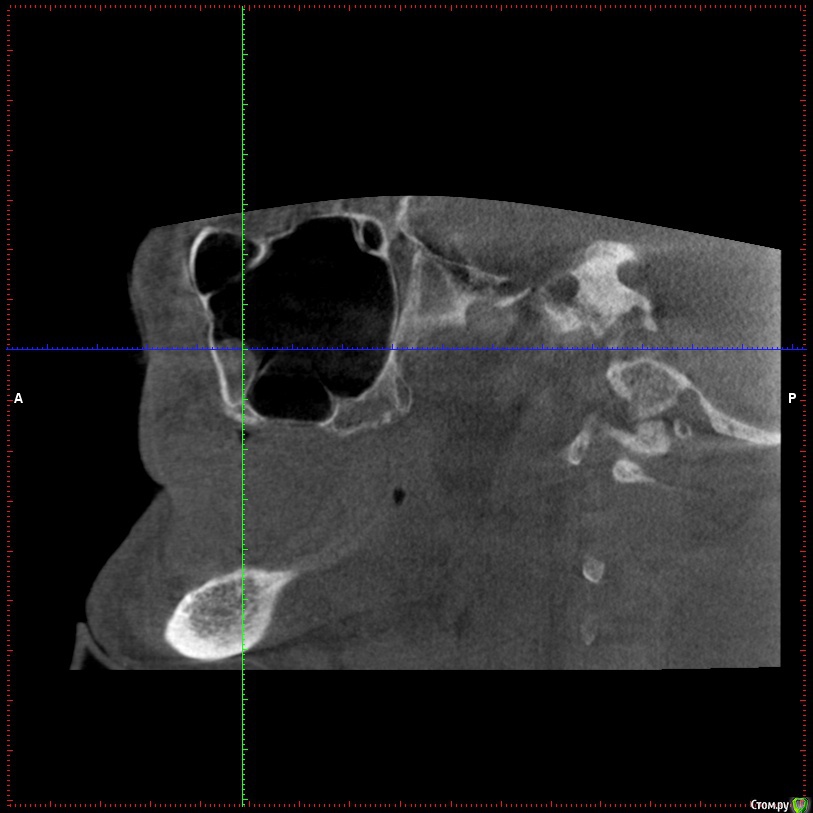

Aleksey_Mironov Опубликовано 11 января, 2018 Поделиться Опубликовано 11 января, 2018 здравствуйте коллеги!! вот такой сюрприз..хочу сделать синус лифтинг.. что за образование можеть быть? Ссылка на комментарий

Aleksey_Mironov Опубликовано 11 января, 2018 Автор Поделиться Опубликовано 11 января, 2018 здравствуйте коллеги!! вот такой сюрприз..хочу сделать синус лифтинг.. что за образование можеть быть? Ссылка на комментарий

Борис80 Опубликовано 11 января, 2018 Поделиться Опубликовано 11 января, 2018 Не совсем уверен, тк недостаточно срезов видно, но я бы сказал насморк или что-либо подобное(это по поводу тени) и , что значительно неприятнее, это костная перегородка на дне пазухи Ссылка на комментарий

колесников Опубликовано 11 января, 2018 Поделиться Опубликовано 11 января, 2018 (изменено) Может образоваться перфорация мембраны. Делайте 2 окна Изменено 11 января, 2018 пользователем колесников Ссылка на комментарий